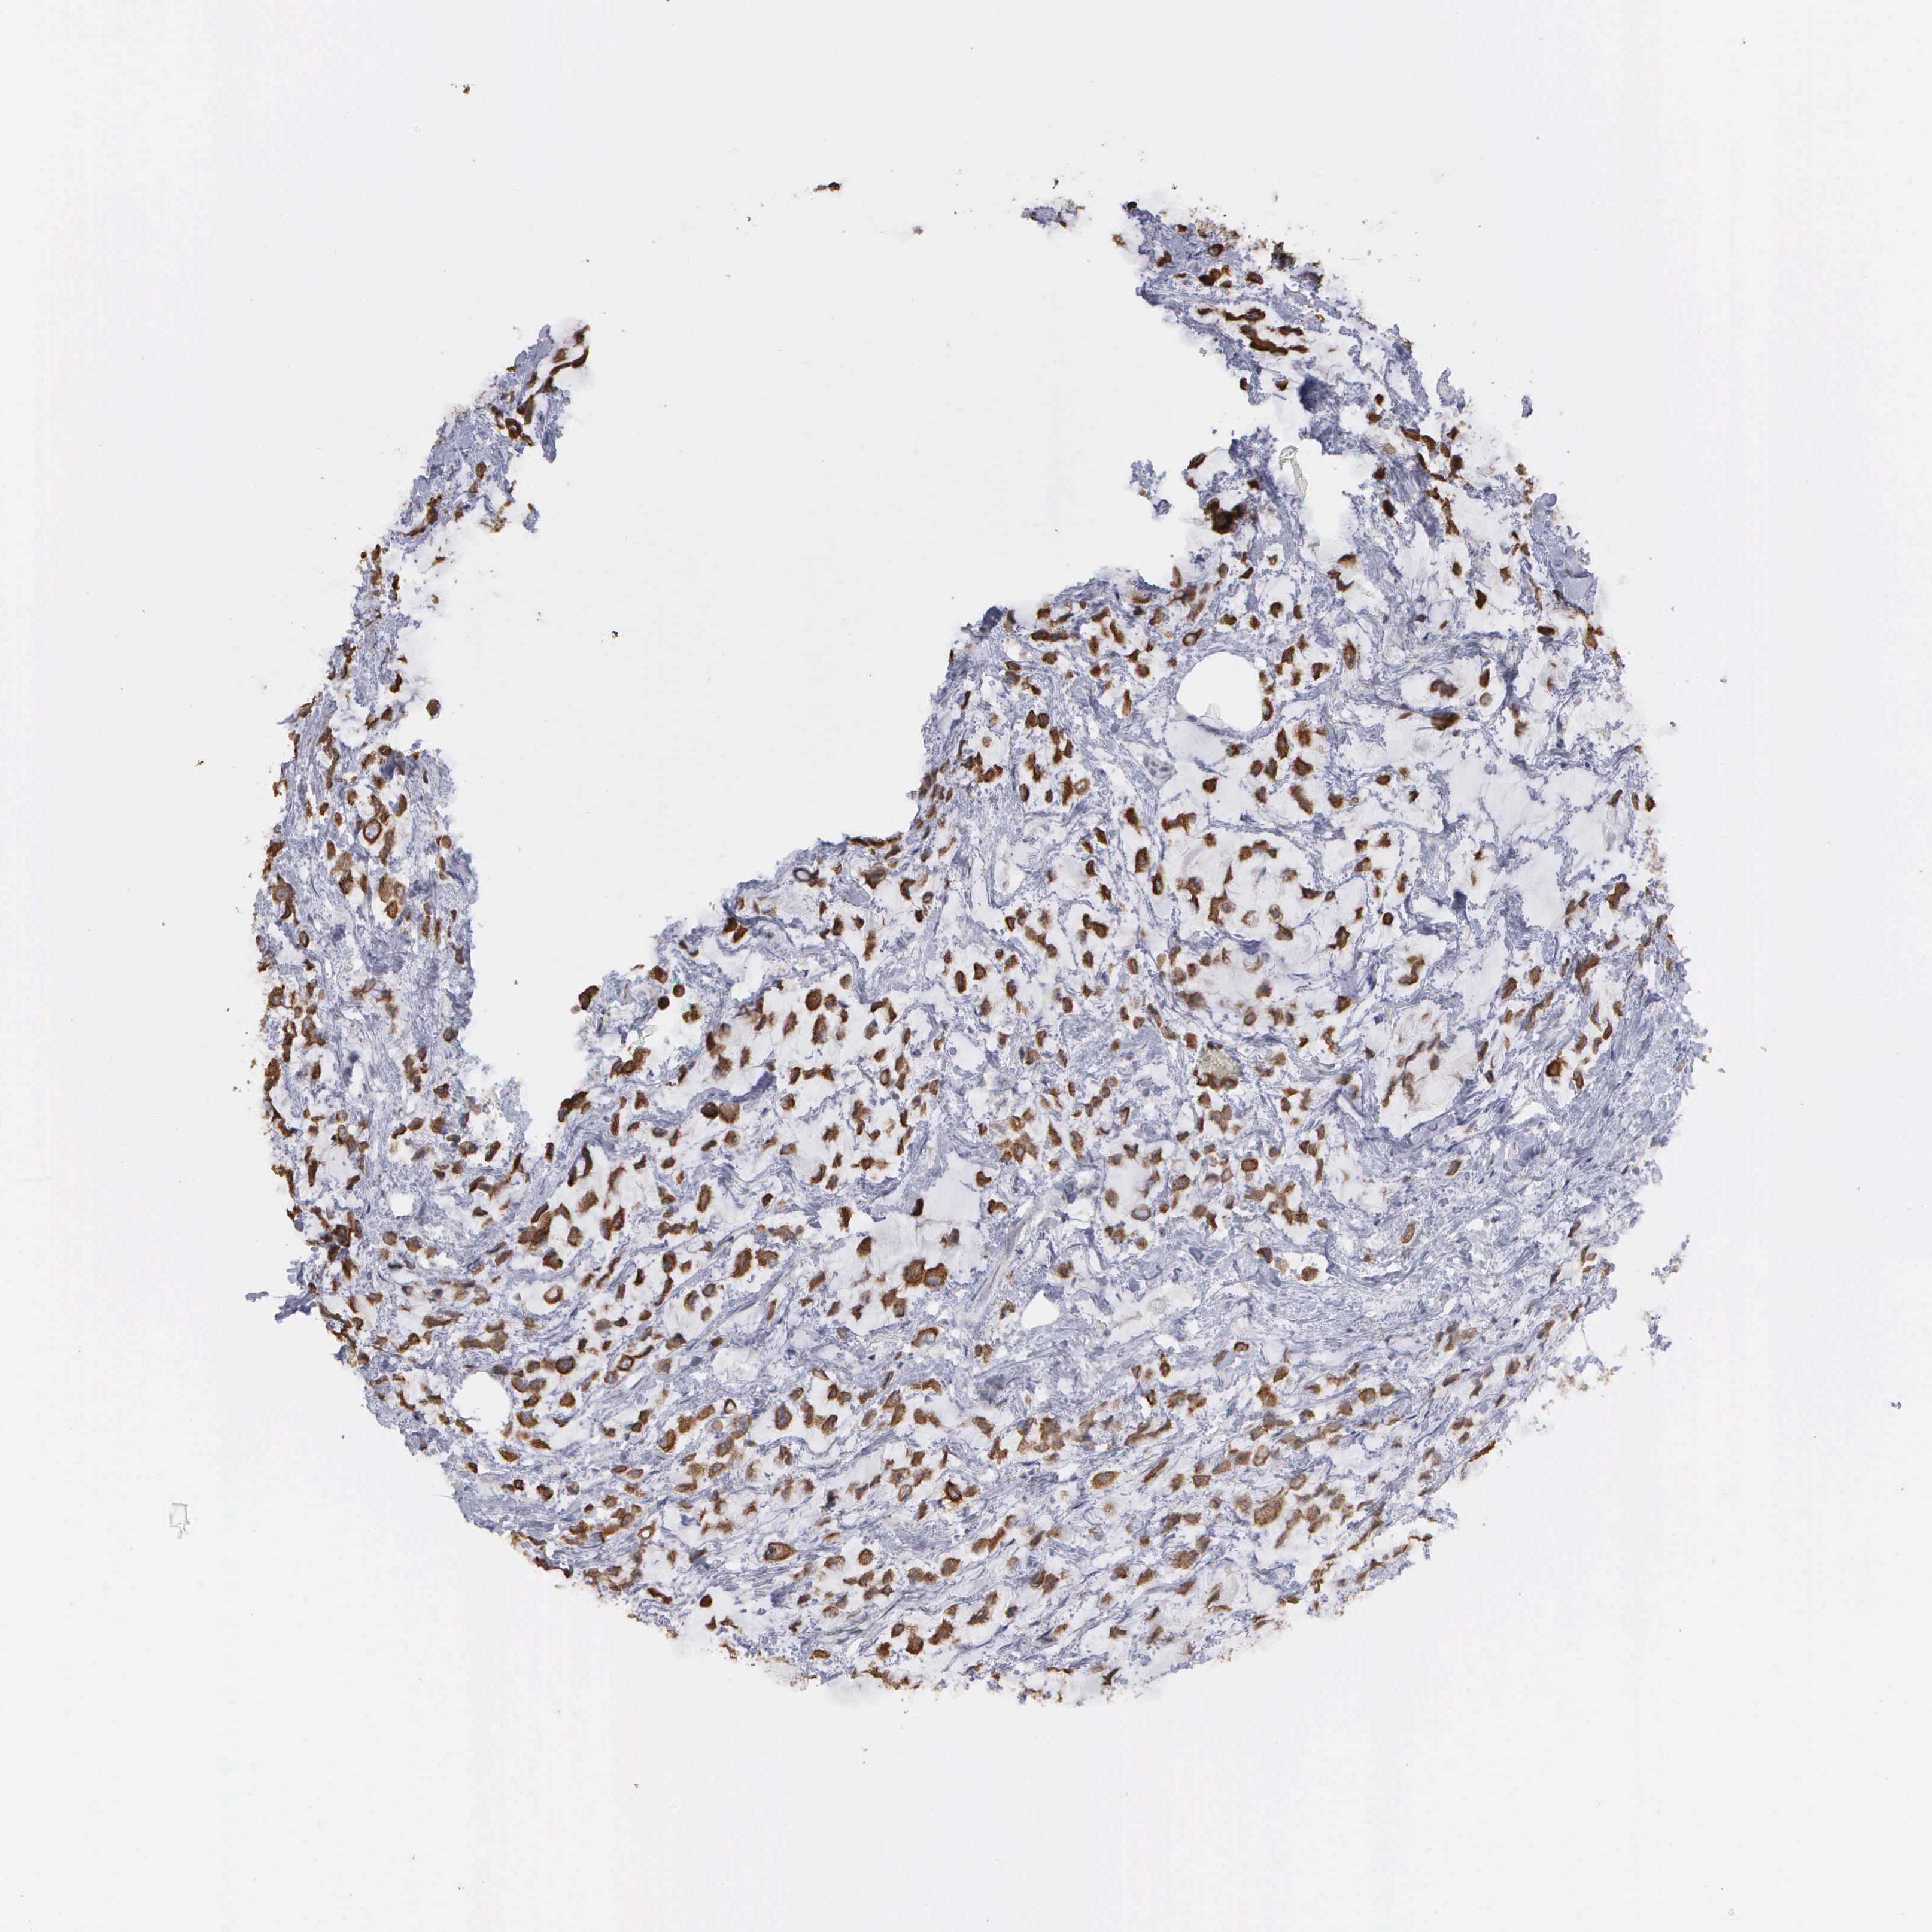

BRCA TCGA BRCA VALIDATION PROTEIN EXPRESSION